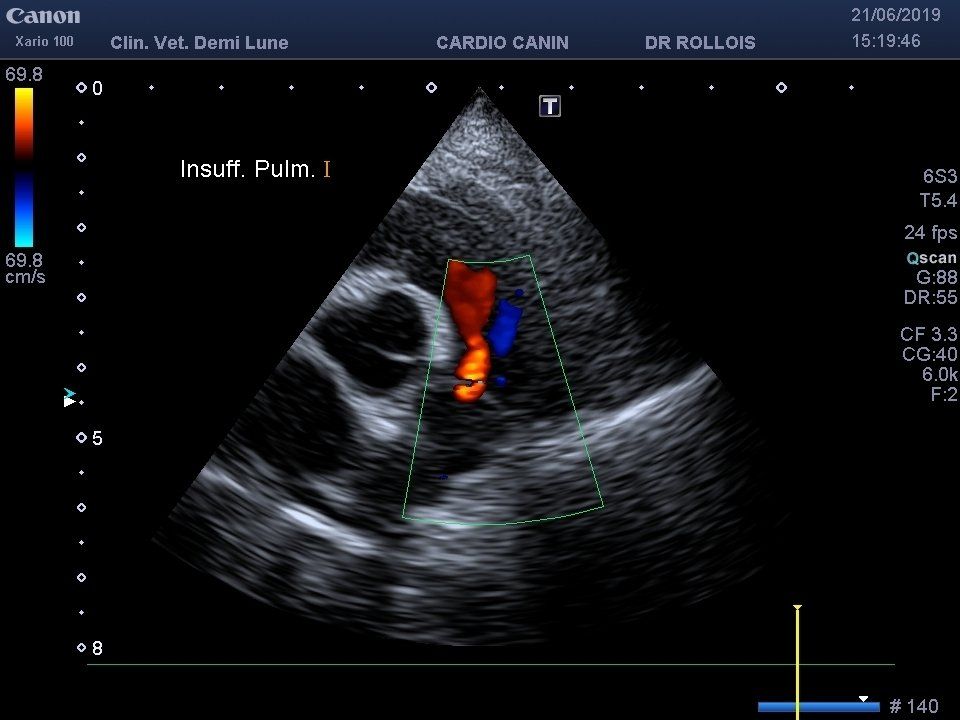

L’échocardiographie est indiquée dans l’exploration et le suivi des maladies cardiaques. Elle permet la visualisation des cavités cardiaques, ainsi que la contractibilité du muscle cardiaque et l’observation de la circulation sanguine. Elle peut être complétée par une mesure de la tension artérielle par un appareil Doppler et la réalisation d’un électrocardiogramme.